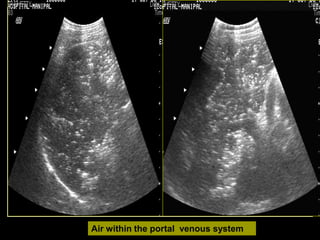

 Air in portal venous system

Air within the portal venous system

Indirect evidence  Rarelyidentification of occlusion of SMA / SMV.  Dilated bowel loops and bowel wall thickening  Pneumatosis intestinalis  Air in portal venous system

Air within theportal venous system